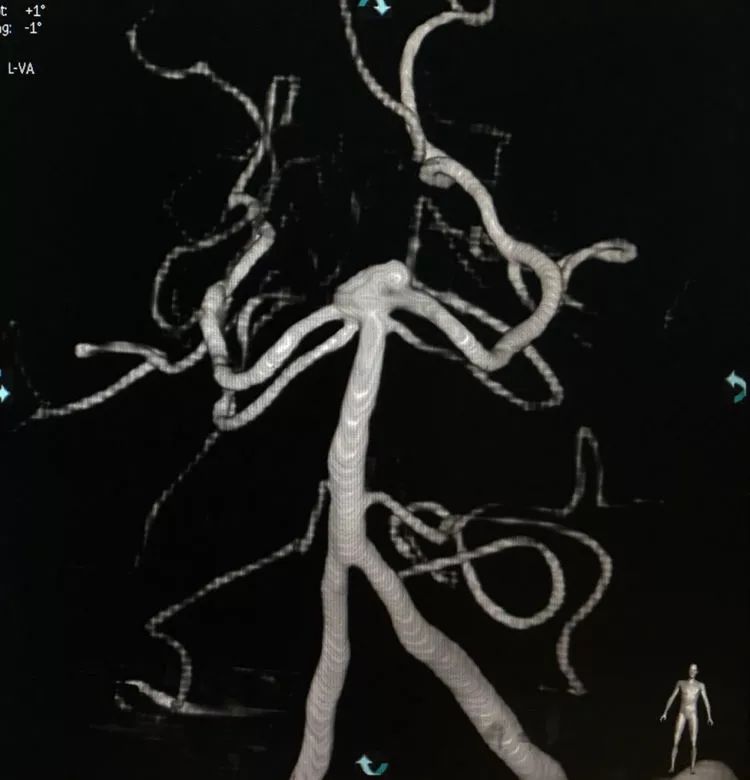

左椎动脉正位造影可以看到指向左方的子瘤。

左椎动脉造影三维重建和测量